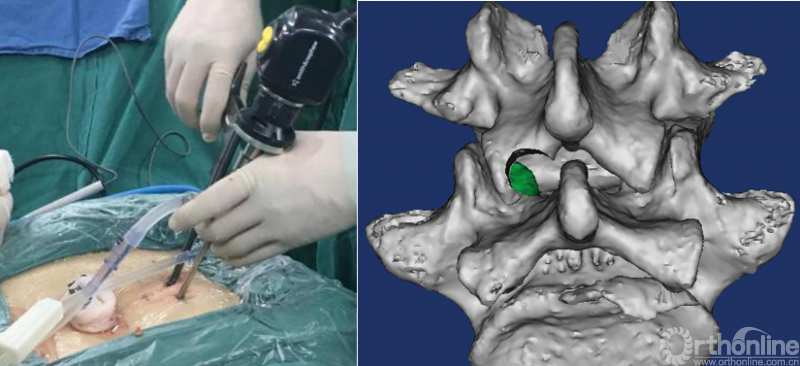

第五步“咬”:咬除部分上关节突,显露椎间盘及神经根;

第六步“切”:切除椎间盘;

第七步“旋”:旋转舌形套管保护神经根;